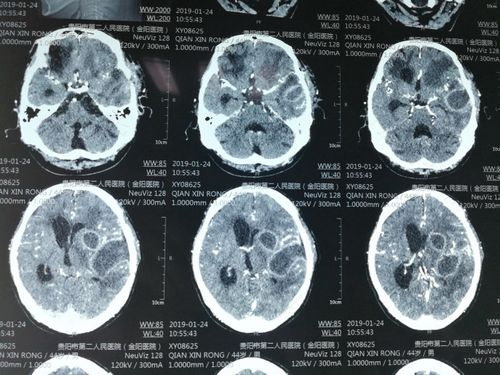

虽然大家都希望身体健康,但是人们总是免不了生病。而且有时候还会患上重病,比如颅脑疾病。有不少疾病都会引起颅内感染,这是一种比较严重的症状,必须要及时的进行治疗。那么,颅内感染的原因是什么呢?

在患有脑部疾病时,也容易引发颅内感染,比如脑膜炎。在发现有颅内感染的情况时,就要及时到神经内科治疗。患者需要做一个血常规检查,以确认发病原因。要是由于病毒感染导致的,应该进行抗病毒治疗,而细菌感染要做抗炎治疗。颅内感染的患者会出现发烧症状,这时候就要使用抗生素。